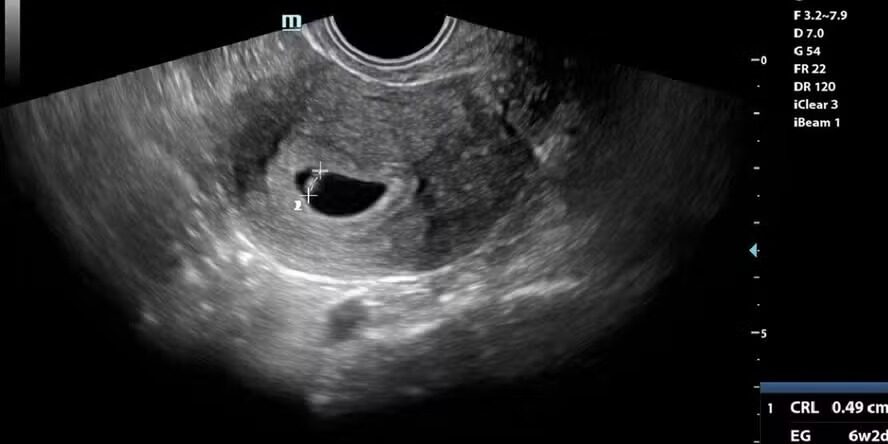

A integração entre inteligência artificial (IA) e robótica médica acaba de atingir um marco histórico: nasceu o primeiro bebê concebido por uma máquina equipada com IA, capaz de realizar o processo de fertilização in vitro com intervenção mínima humana. A notícia, divulgada recentemente pela Revista Galileu, reforça o papel transformador da automação no setor da saúde.

Segundo a publicação, o procedimento foi realizado por um braço robótico guiado por uma inteligência artificial treinada para inserir um espermatozoide no óvulo com precisão. O experimento aconteceu em uma clínica na Espanha e representa um avanço significativo para a fertilização assistida um campo onde precisão e controle são cruciais.